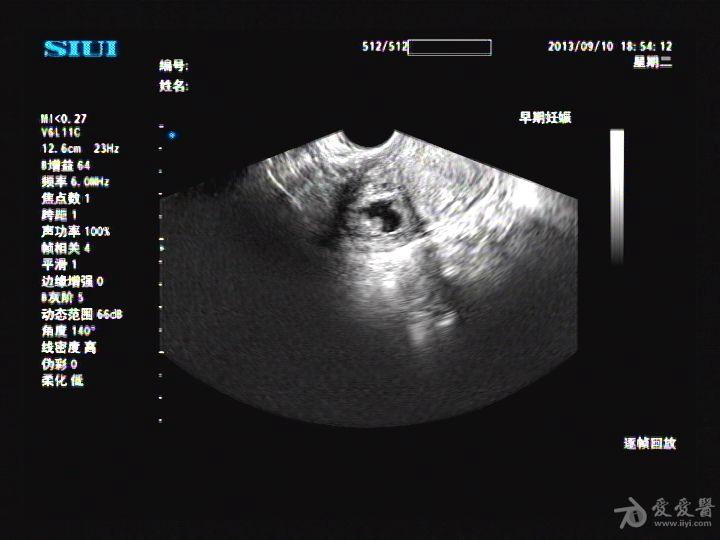

彩超 宫外孕

彩超 宫外孕,

宫内合并宫外孕 超声疑惑

【贴图】宫外孕

一例宫内孕合并宫外孕的彩超

妇产科宫腔镜治疗 写美篇 患者高某,25岁,9月5日来我院彩超室就诊

宫外孕图片